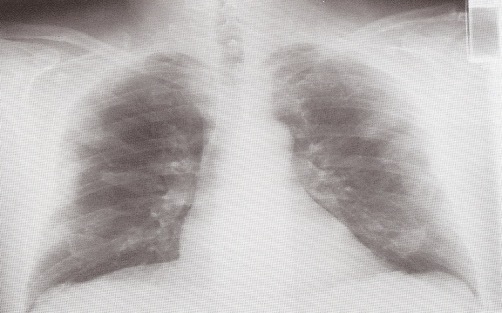

What features are seen on this CXR? What is the likely diagnosis?

Lung markings absent on left

Pneumothorax